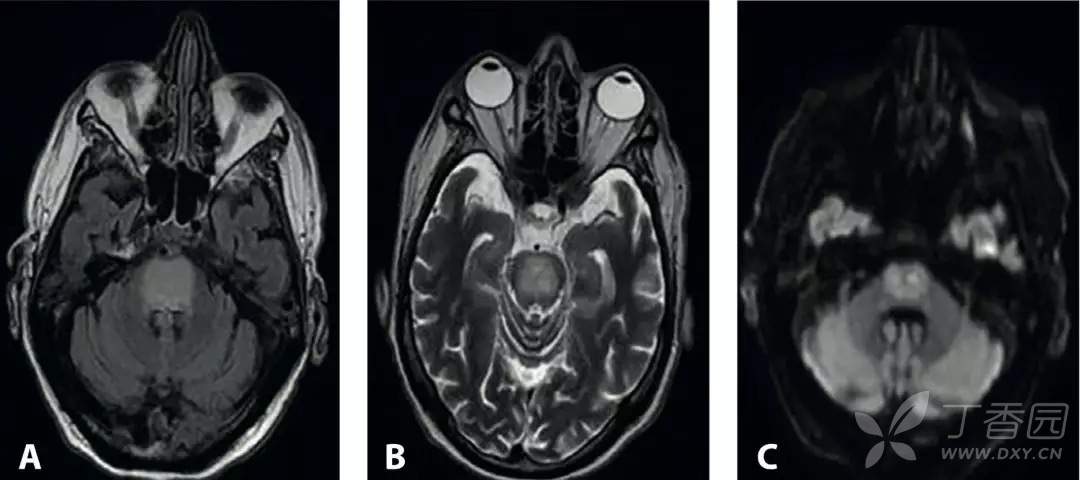

在接下来的一周里患者的血钠每天升高大约1 ~ 3 mmol/L。血钾很快就恢复正常。在这段时间里,患者出现共济失调,静止性震颤和臀部平衡失调(disturbance in rump balance)。MRI如下图: